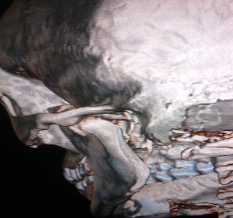

Figure 3. Case 2: Axial CT showing vertical fracture of left condyle of mandible’

Figure 4. Case 2: 3D CT showing vertical fracture of left condyle of mandible.